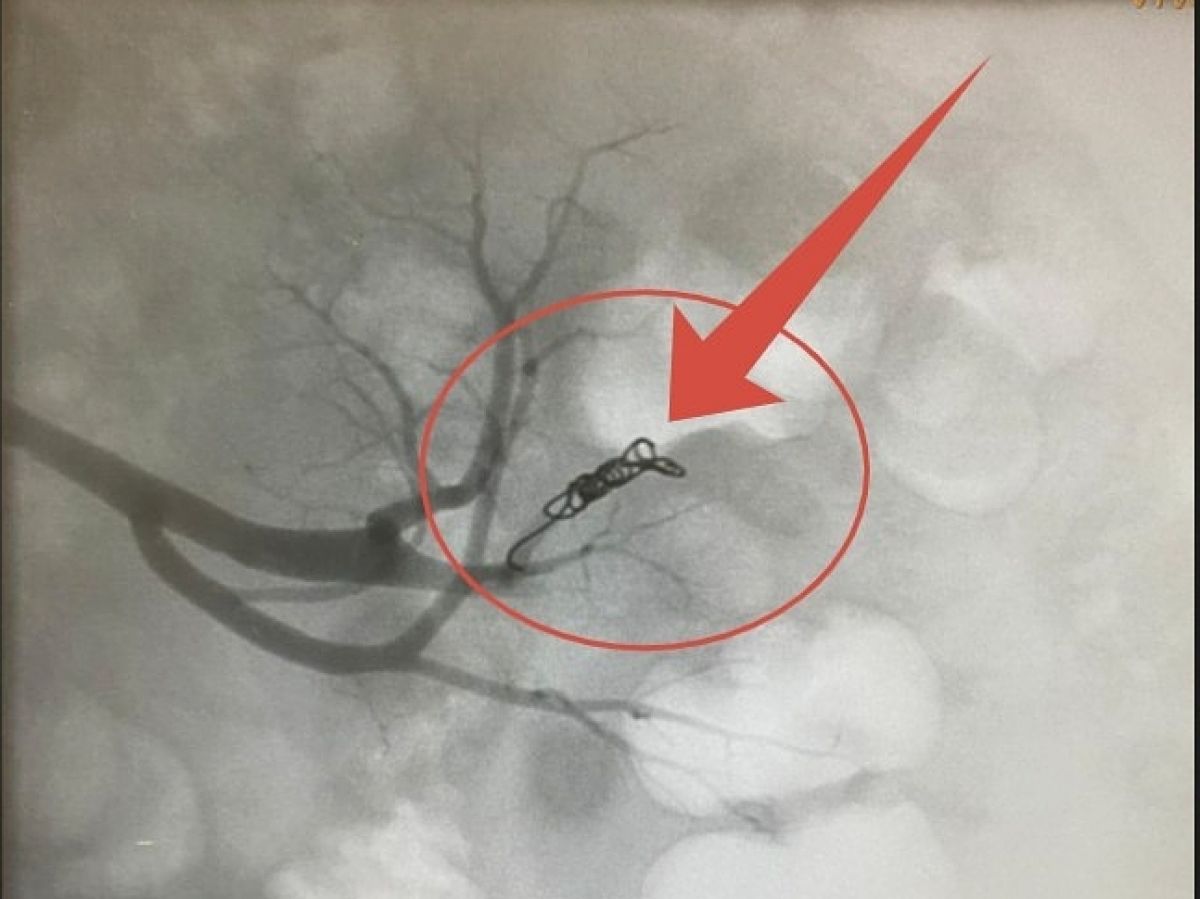

Эндоваскулярные хирурги вместо полостной операции провели высокоточное внутрисосудистое вмешательство. С помощью современного рентген-оборудования врачи смогли «увидеть» сосуды изнутри и обнаружили источник проблемы – поврежденную ветвь почечной артерии.

Не делая больших разрезов, хирурги выполнили эмболизацию сосуда: искусственно заблокировали его, прекратив кровотечение. Процедура прошла успешно, осложнений не последовало.